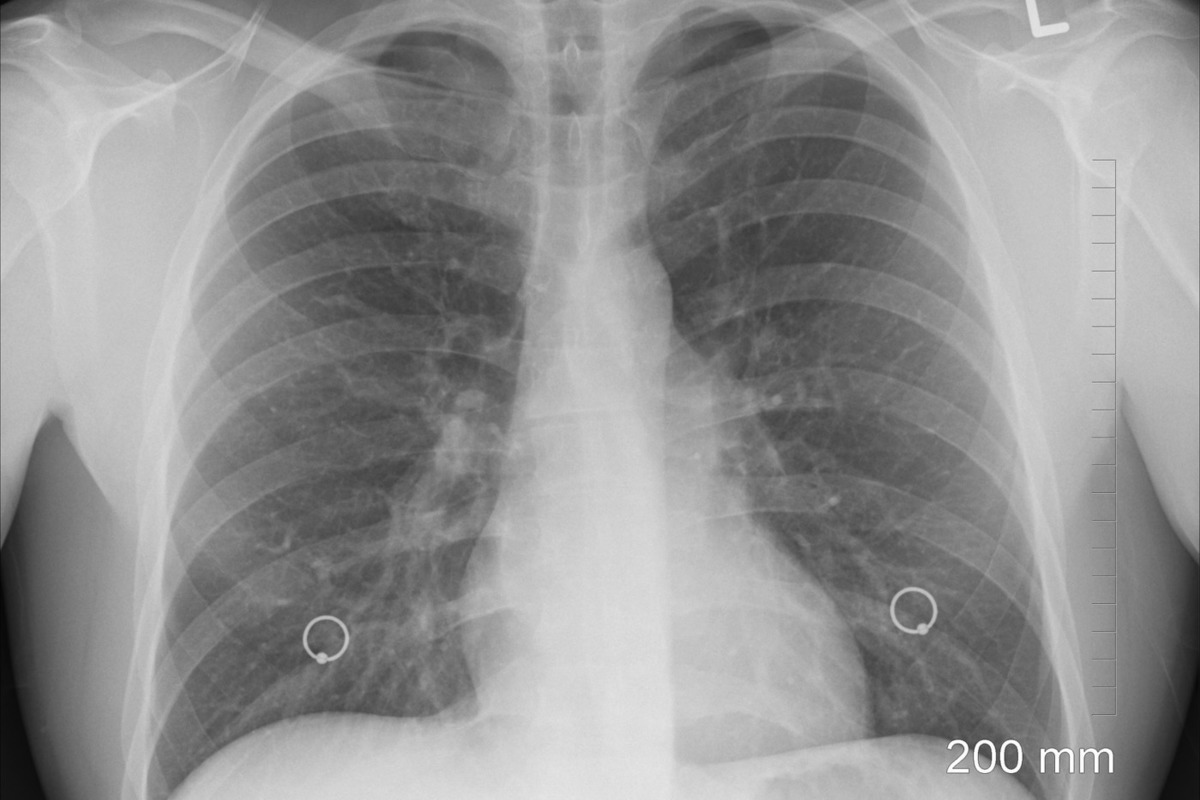

Появляется все больше данных, что COVID может давать осложнения на легкие и приводить к инвалидизации. В частности, один футболист, перенеся инфекцию в нетяжелой форме, получил такое осложнение – теперь футбол для него закрыт. Заведующая кафедрой инфекционных болезней Первого МГМУ им. Сеченова Елена Волчкова рассказала "МК", о чем идет речь.

"Чем больше при COVID поражена легочная ткань, тем хуже ситуация. В ряде случаев она замещается грубой соединительной тканью, поэтому в легкие попадает меньше кислорода и начинаются проблемы с работой сердца и сосудов. Поэтому чем раньше выявили заболевание и начали лечение, тем меньше вероятность, что легкие будут глубоко поражены", - рассказывает Елена Волчкова.

Такие осложнения при пневмониях случаются, разумеется, не только при коронавирусной инфекции, но и при массе других. "Это бывает при гриппе, например, особенно, при пандемическом гриппе H1N1, который холит в этом году тоже. Там тоже в некоторых случаях развиваются атипические пневмонии, при которых поражается альвеолярное древо. К сожалению, эти изменения носят необратимый характер".

Последние данные показали, что чаще такие осложнения развиваются у мужчин. Еще один фактор риска – курение.